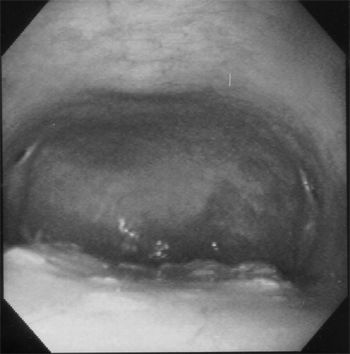

A new development in the diagnosis of upper airway disease